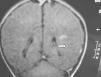

A los 4 meses de vida se constató una hemiparesia derecha por lo que se realizó RM cerebral, presentando atrofia de la mayor parte del lóbulo parietal izquierdo y del tálamo del mismo lado con múltiples cavidades porencefálicas en el territorio de la arteria cerebral media izquierda. Se observaba así mismo un ensanchamiento del ventrículo lateral derecho (figs. 4 y 5). La angio-RM está pendiente de realización.

Figura 4.T2 axial. Atrofia de la mayor parte del lóbulo parietal izquierdo y del tálamo de ese lado.